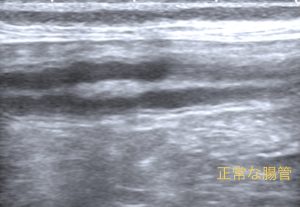

超音波検査を行ったところ、回腸から盲腸、結腸にかけて腸の肥厚と構造の破壊が認められました。腫瘍の可能性も考慮されたため、CT検査と手術(回盲部切除)を行いました。